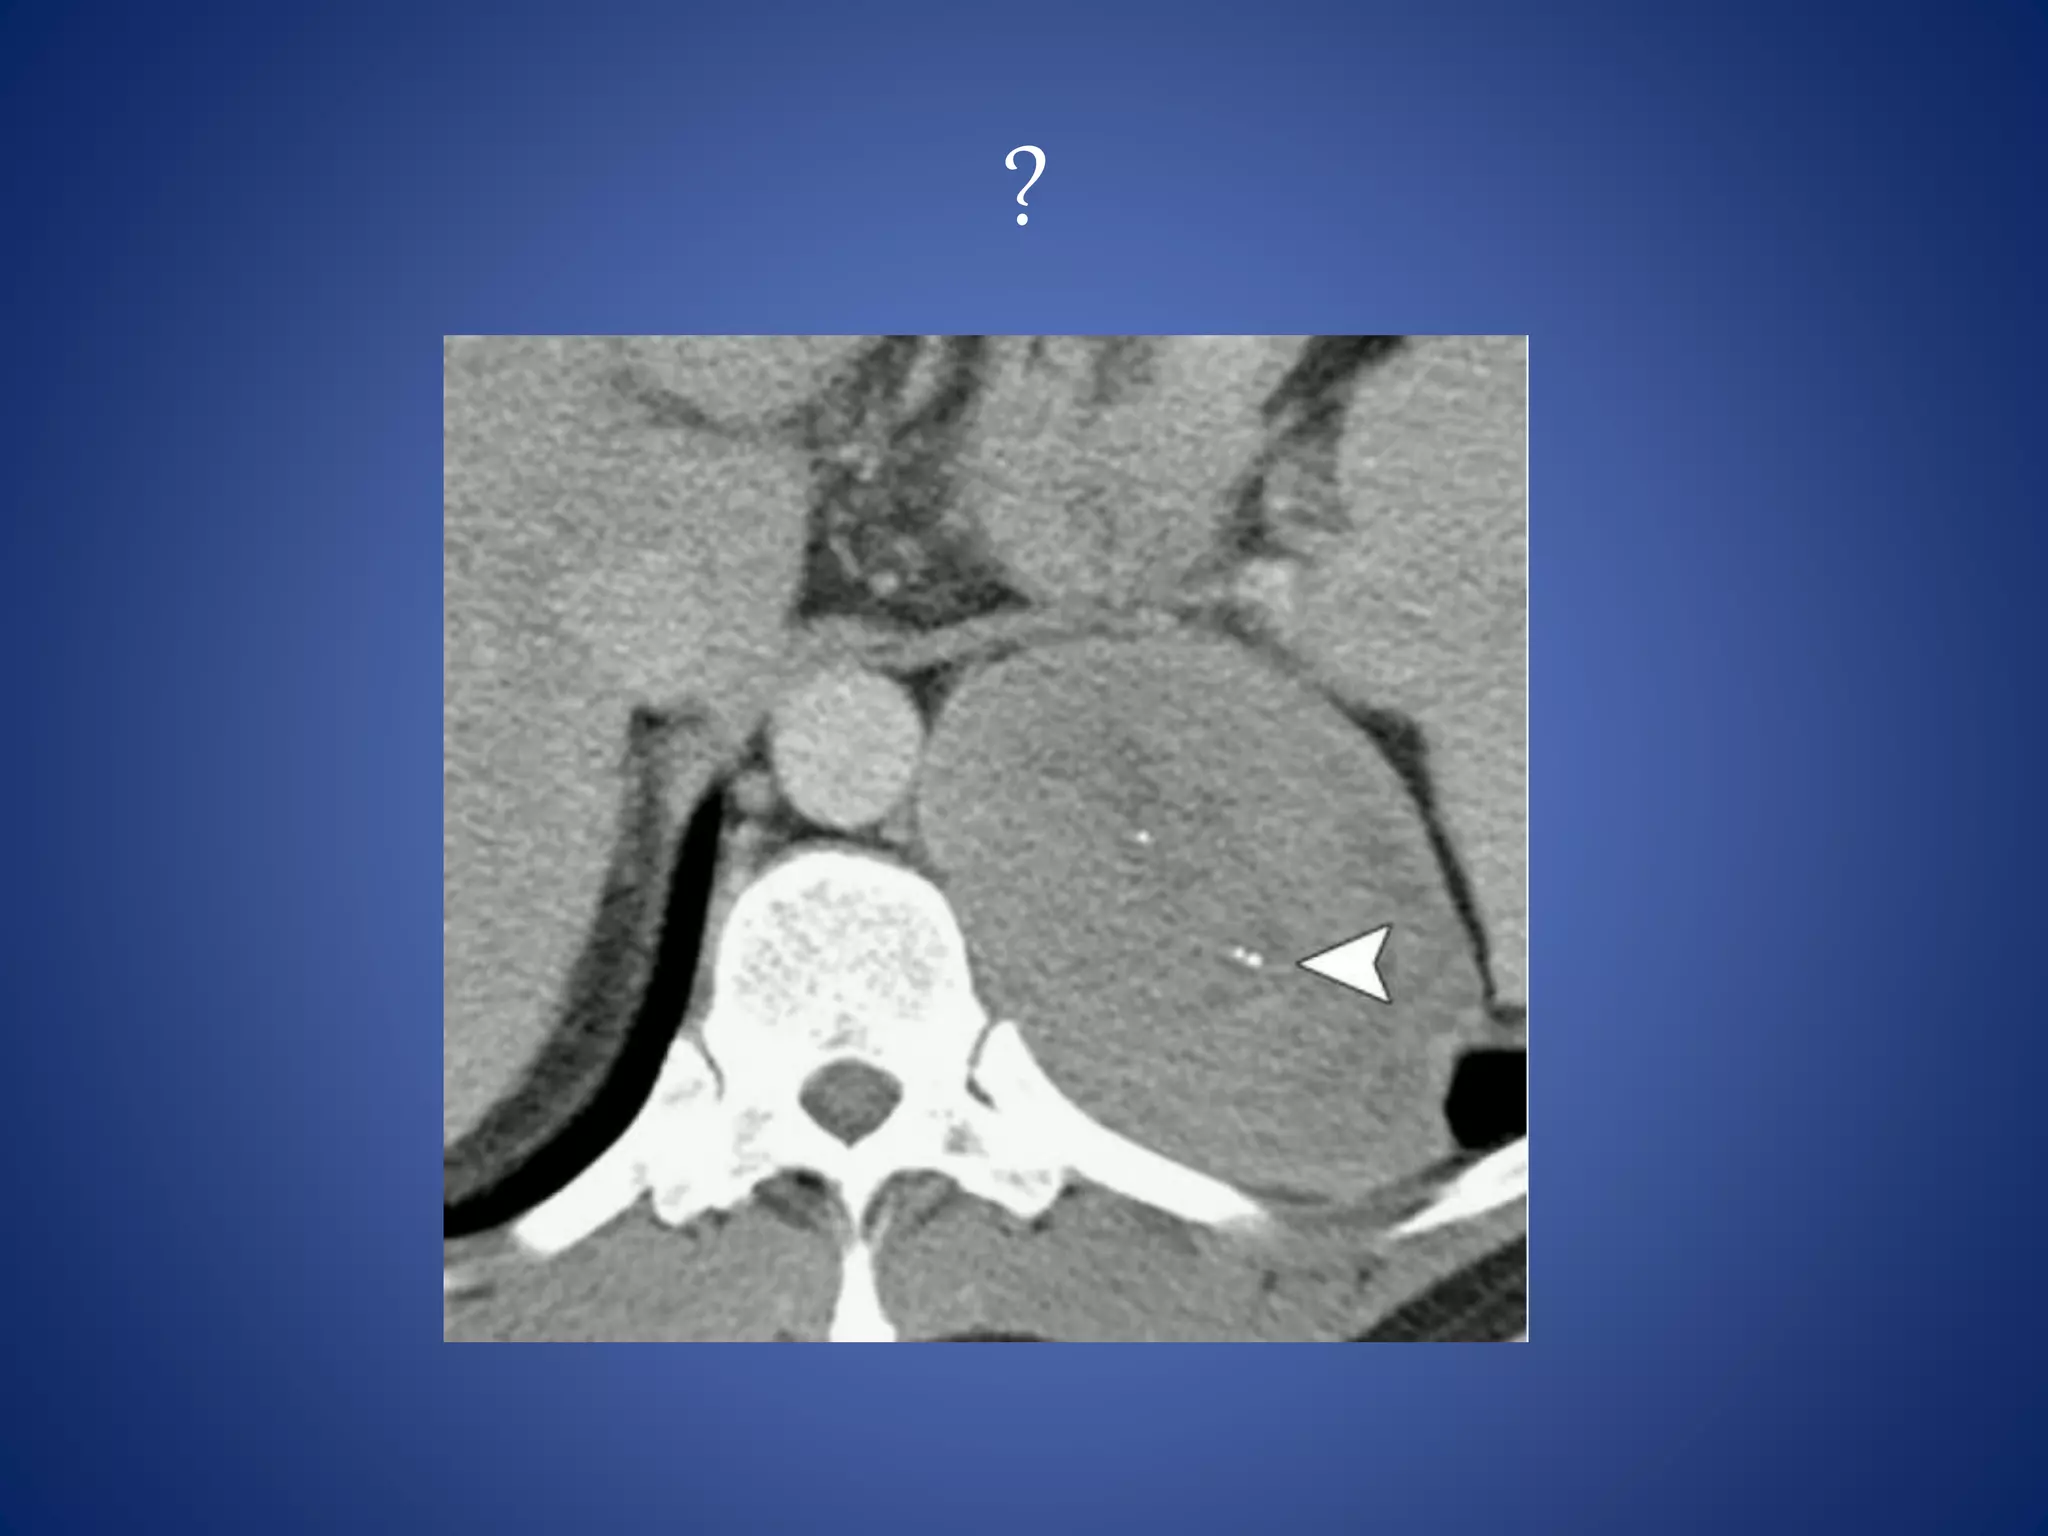

Liposarcoma

Liposarcoma is the most common (33%) primary retroperitoneal

sarcoma.

Liposarcoma is usually large (average diameter, >20 cm) and is a slow-

growing tumor.

It is a predominantly hypoattenuating lesion on CT because of its fat

content. At MR imaging, it follows fat signal.

The appearance of liposarcoma may be similar to that of a lipoma,

but liposarcoma has thicker, irregular, and nodular septa that show

enhancement after contrast material administration.

Lipoma is less common than liposarcoma in the retroperitoneum.

Occasionally, a portion of the well-differentiated liposarcoma

undergoes histologic dedifferentiation and becomes more aggressive

and metastatic and then carries a worse prognosis.

At CT and MR imaging, these dedifferentiated tumors are depicted

as heterogeneous tumors with both fat and solid components and

show a lack of clear delineation

between solid and fat components.

Calcification is seen in as many as

30% of cases and is an important

sign of dedifferentiation.

• #11 Well-differentiated liposarcoma in a 58-year-old woman is shown as a large homogeneous fat-containing mass with thick septa (arrows) that show soft tissue attenuation.

• #12 In a 65-year-old woman, mixed pattern is shown in a dedifferentiated liposarcoma that contains fat (arrowhead) and a large enhancing soft-tissue component (arrow)

• #73 Liposarcoma --- Large retroperitoneal mass predominantly of fatty attenutation with irregular nodular septations The appearance of liposarcoma may be similar to that of a lipoma, but liposarcoma has thicker, irregular, and nodular septa that show enhancement after contrast material administration.